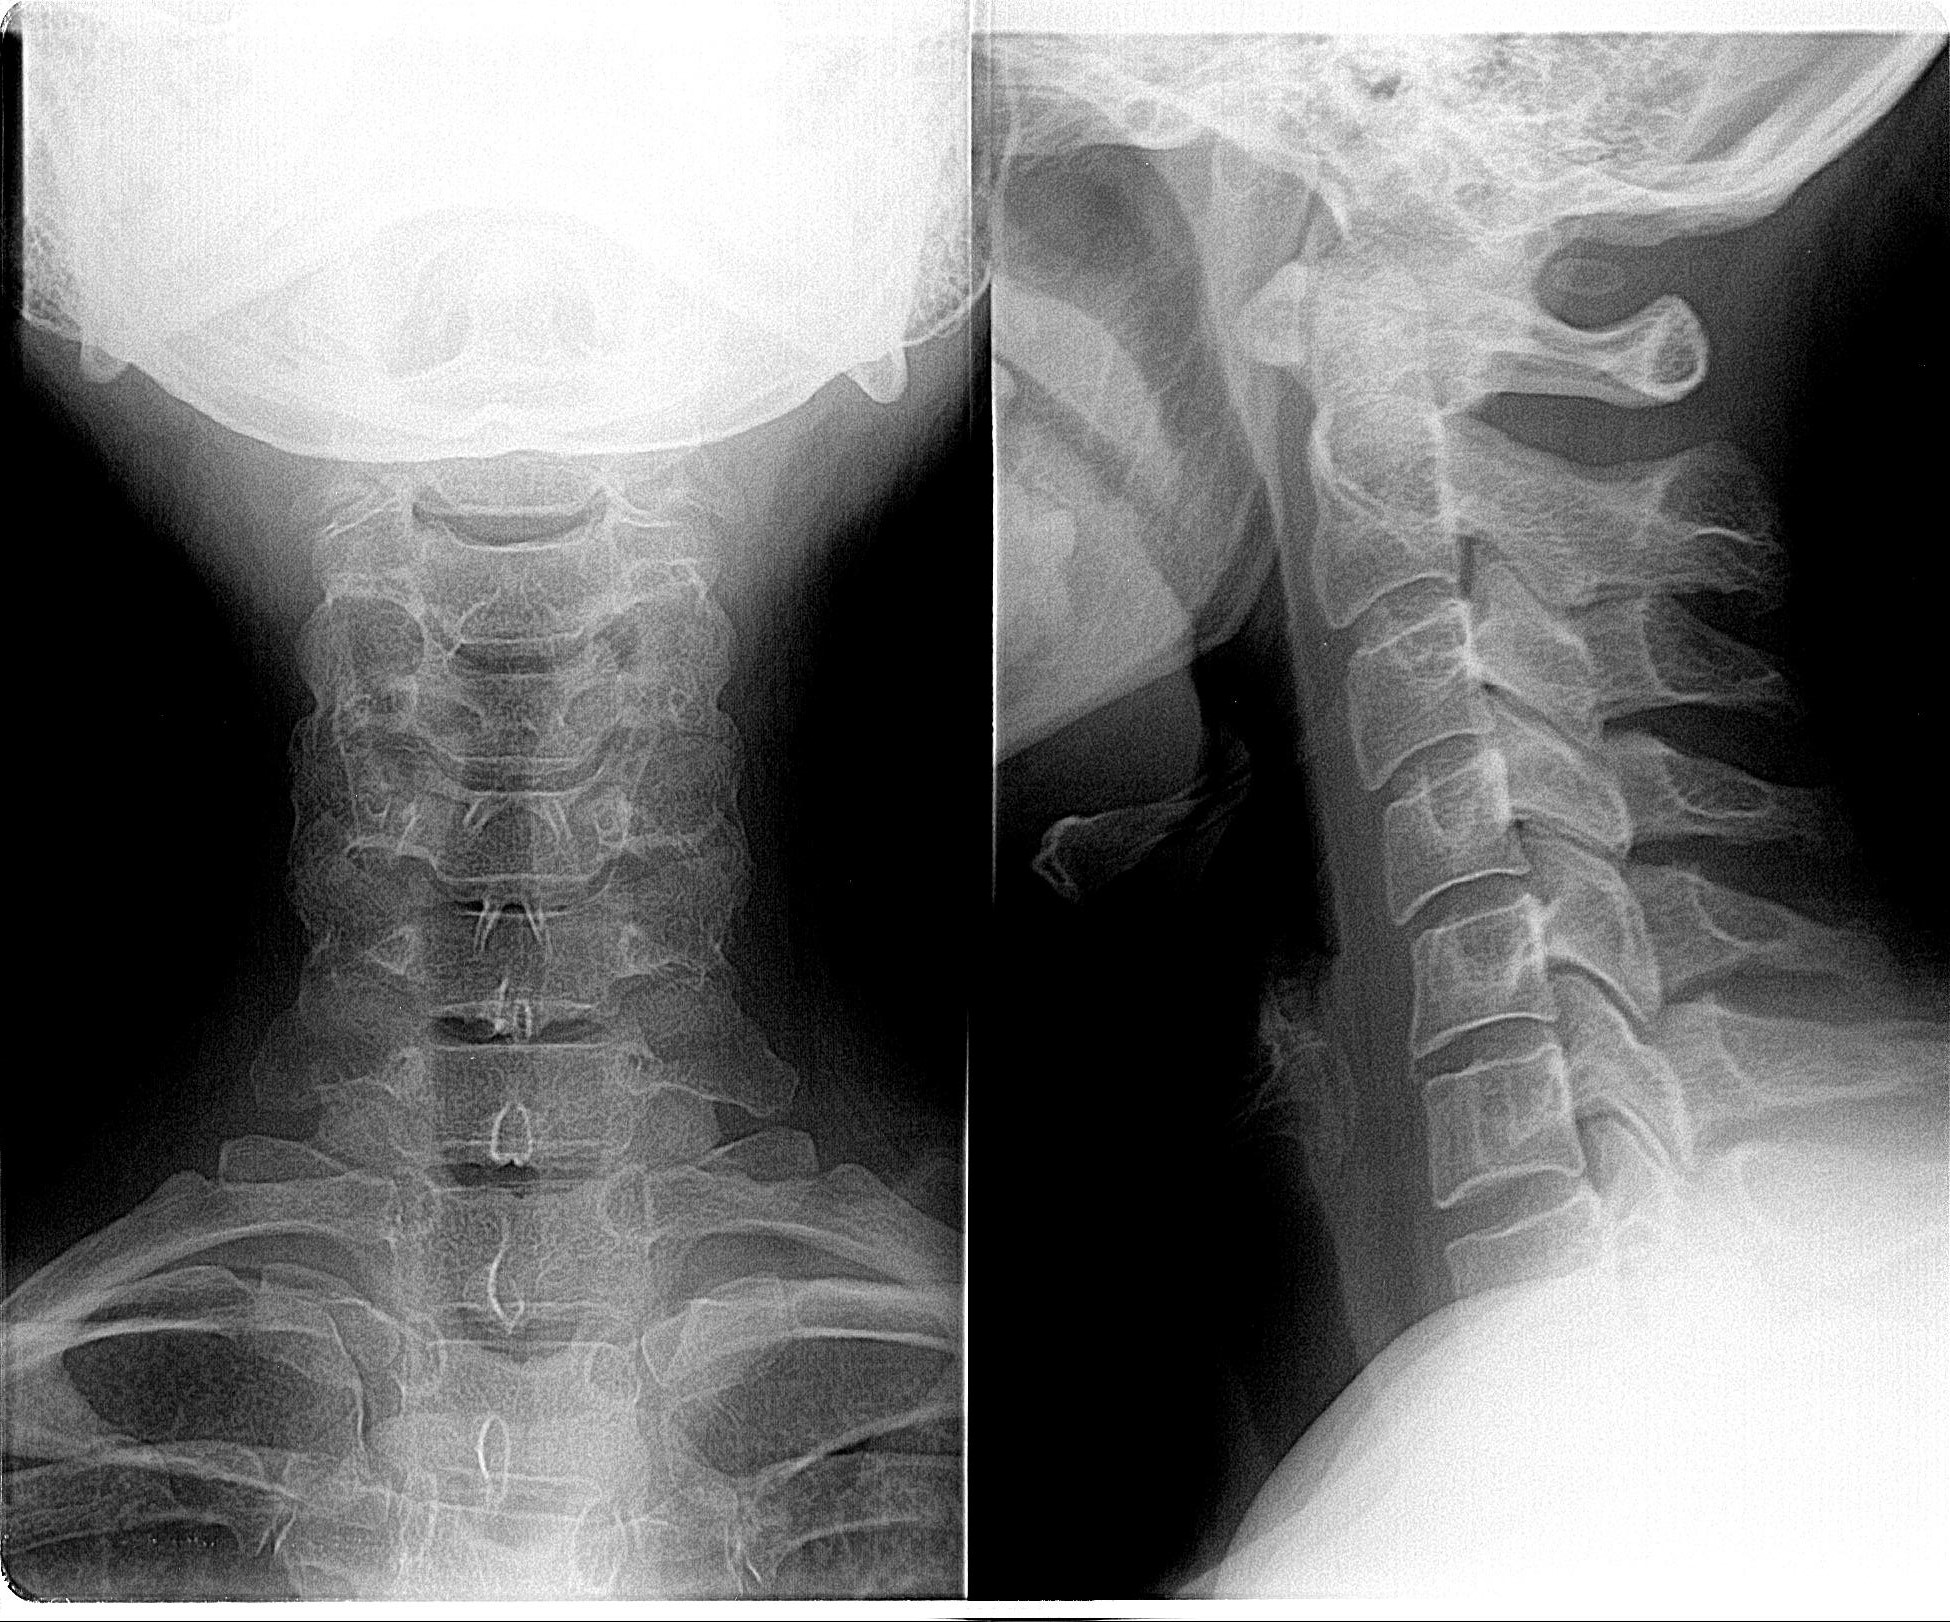

Рентген поясницы: анатомические особенности и медицинские исследования

Раздел: Фотоэссе